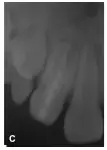

2牙冠異常,牙根較正常牙粗大,管腔大,根管內(nèi)有似牙釉質(zhì)牙本質(zhì)密度影像,中央有一空腔,形態(tài)似一小牙,內(nèi)陷根管根尖發(fā)育基本完成,主根管牙根形成2/3,根尖呈喇叭口狀,處于NollaVIII期,根尖周有低密度影像;2牙冠異常,處于NollaVI期(圖1A)。

圖1A:2,2牙冠異常,2根尖周低密度影像;

2開髓,揭頂,大量膿液從根管內(nèi)滲出,探查根管發(fā)現(xiàn),內(nèi)陷的牙釉質(zhì)與正常牙本質(zhì)緊密相連,擴(kuò)大針無法從二者之間進(jìn)入主根管,而通過內(nèi)陷的中央管腔可以到達(dá)主根管(圖1B)。拔髓不成形,通暢根管,生理鹽水沖洗,CP開放引流,囑口服阿莫西林0.25g/Tid。沖洗換藥1次/3d,換藥2次后右上唇及頜面部腫脹消失,疼痛緩解。內(nèi)陷根管封Vitapex 1周后,30號擴(kuò)挫,Vitapex充滿內(nèi)陷根管,磷酸鋅水門汀封洞。以后前3個月每隔1個月更換Vitapex1次(圖1C),后12個月每隔3個月更換Vitapex 1次。

圖1B:2內(nèi)陷根管插牙膠尖片;C:2 Vitapex充填內(nèi)陷根管5個月后根尖暗影消失;